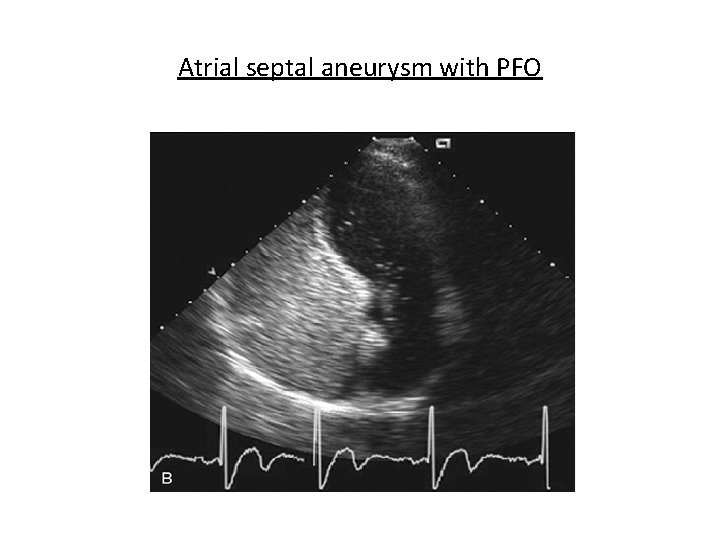

Atrial septal aneurysm with PFO

Shunt Detection • Right-to-left shunts - agitated saline - agent of choice – Atrial septal defects of all types – Patent foramen ovale - Valsalva and cough – Pulmonary arteriovenous malformations - 5 to 15 cycles – Larger ventricular septal defects during diastole – Left SVC • Left-to-right shunt – Negative contrast effect